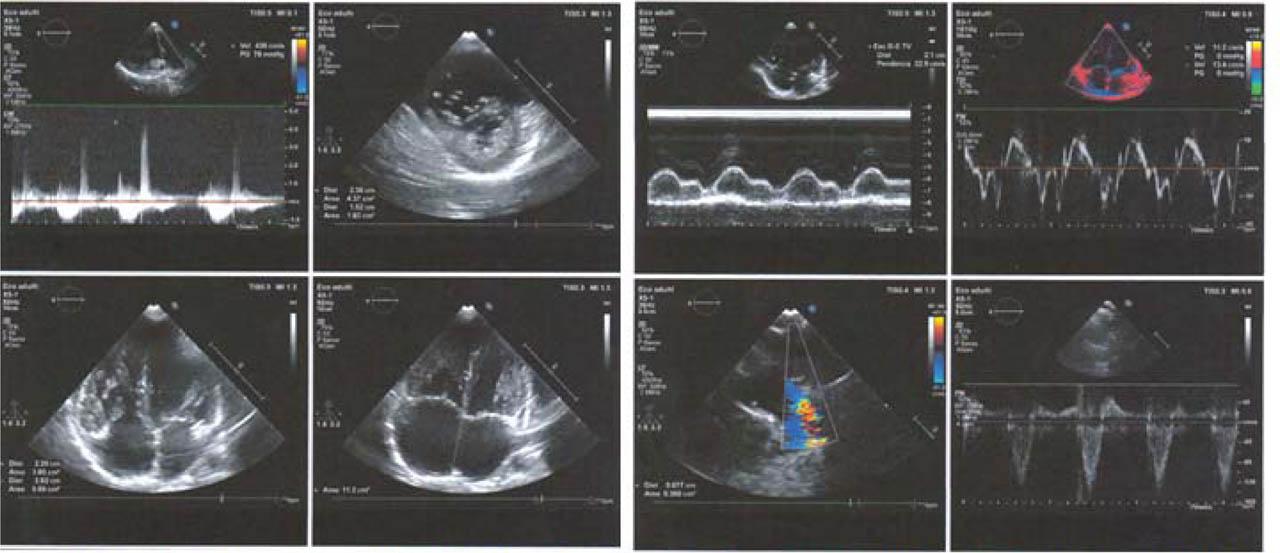

Figure 1